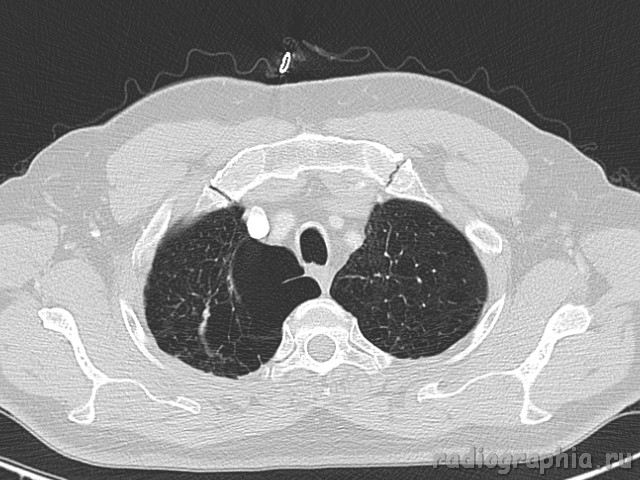

Одиночный узел правого лёгкого.

На рутинном снимке ОГК, был выявлен одиночный узел; по протоколу выполнили КТ. Какое было бы ваше заключение; и как бы Вы поступили если у вас нет возможности выполнять КТ?

Routine Chest X-Ray. SPN (solitary pulmonary nodule-red arrow)